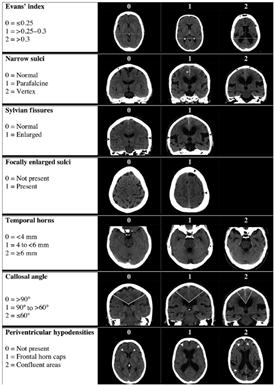

Ovenstående radiologiske fund kan vurderes semikvantitativt ved enten DESH score eller Radscale som en checkliste for iNPH karakteristika og for gradering af sværhedsgraden af de radiologiske forandringer (Appendix 1)

- Vurdering af iNPH specifikke radiologiske fund med anvendelse af valideret skala, her anbefales enten DESH score eller Radscale, som er semikvantitative skalaer udviklet til iNPH

DESH Skala (Shinoda et al., 2017)

RAD scale (Kockum et al., 2017)